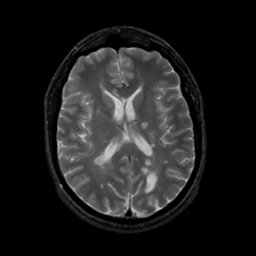

MR Study #8, March 31, 1991 -- Slice #29

[Home][Help][Clinical][Tour 1][Tour 2] Slice 29